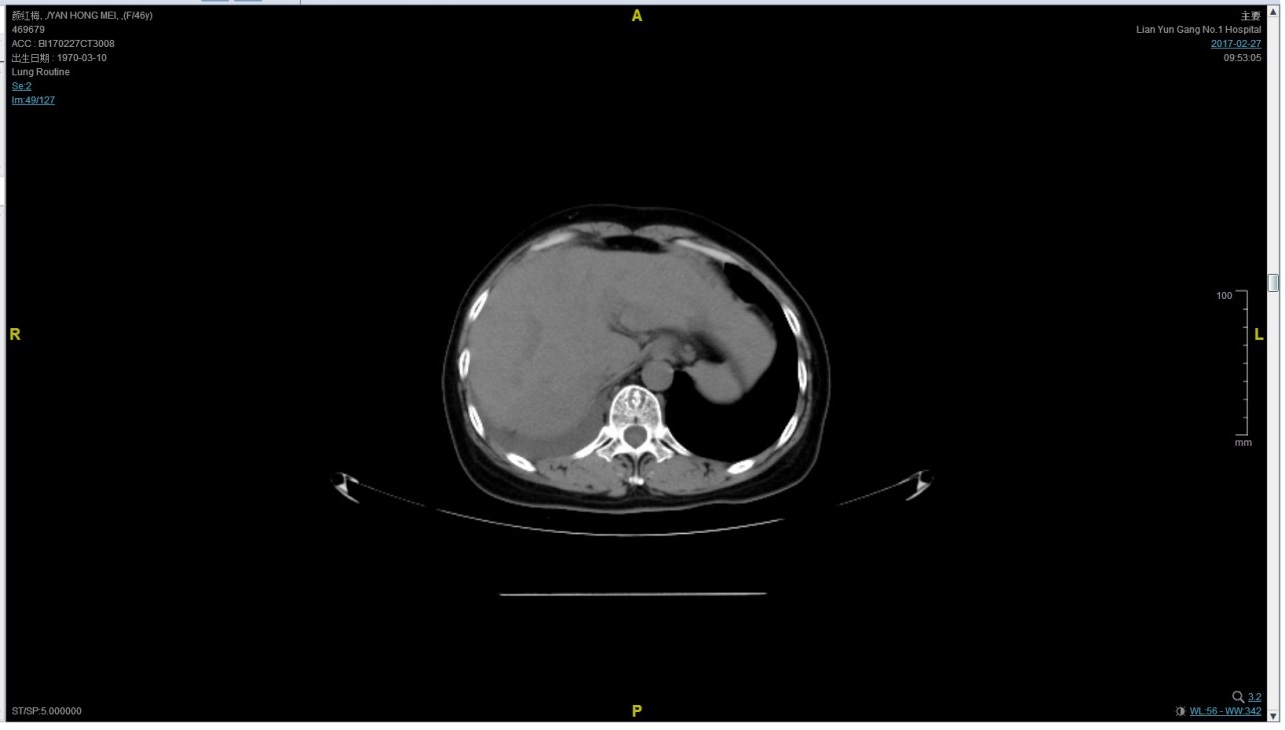

2017-02-27患者因气喘胸闷再次就诊。患者肺部病灶进展,同时出现肝脏转移。再次给予曲妥珠单抗+长春瑞滨化疗一周期,效果不佳,推荐换用TKI治疗,患者放弃治疗。PFS3=12个月。

患者颜X X,女,发病年龄43岁。2010.12.01因体检发现右乳质硬、无痛性肿块住院治疗。入院查体肿块约2.5cm × 1.5cm。考虑诊断为右侧乳腺癌。2010.12.06在我院全麻下“右乳癌改良根治术”。术后病理:(右)乳腺浸润性导管癌,组织学分级Ⅲ级;乳头、皮肤未见癌累及,同侧腋窝淋巴结转移(19/19)。免疫组化:ER(-),PR(-),C- erbB-2(3+)。术后诊断右乳浸润性导管癌并右侧腋窝淋巴结转移(pT2N3M0,IIIC期,HER2阳性型)。术后于2011-01-06起在连云港市第一人民医院给予AC方案化疗4周期,2011-03-20给予右胸壁+右锁骨上下淋巴引流区放疗Dt50Gy/25f,2011-05-26予TH方案化疗4周期(曲妥珠单抗d1首次480mg,以后360mg)共4周期。后续予以曲妥珠单抗360mg(每21天为一周期)维持治疗1年,末次使用曲妥珠单抗的时间在2012年5月,后定期随访,病情稳定。2013-11-23全面复查发现肺转移。 DFS=35个月。2013-11-26起给予曲妥珠单抗(440mg d1)/脂质体紫杉醇(240mg d2)/CBP(500mg d2)方案化疗一个周期,出现Ⅱ度骨髓抑制,因患者主诉乏力明显,后修改方案曲妥珠单抗(330mg 每 3周重复)/脂质体紫杉醇(120mg d1+d8+d15,每4周重复)化疗,化疗过程顺利,患者无明显骨髓抑制,无乏力主诉,于2014-02-11全面复查,疗效评价为PR。继续曲妥珠单抗+脂质体紫杉醇(共六周期)治疗,疗效评价CR。后续予以曲妥珠单抗维持治疗,随访病情稳定。2015年4月,患者肺部病灶复发。给予曲妥珠单抗+希罗达治疗(希罗达1500mg,一天两次口服)。PFS1=17个月。2016-2-18,肺部病灶进展,肺内转移病灶增多。PFS2=10个月。从2016-2-19开始给予紫杉醇+曲妥珠单抗治疗,紫杉醇240mg,3周重复,曲妥珠单抗330mg三周重复。患者末次应用曲妥珠单抗和紫杉醇时间为2016-6-24,紫杉醇共应用4周期。CT评价SD。继续曲妥珠单抗维持治疗,且自服中药。2017-02-27患者因气喘胸闷再次就诊。患者肺部病灶进展,同时出现肝脏转移。再次给予曲妥珠单抗+长春瑞滨化疗一周期,效果不佳,患者放弃治疗。PFS3=12个月。